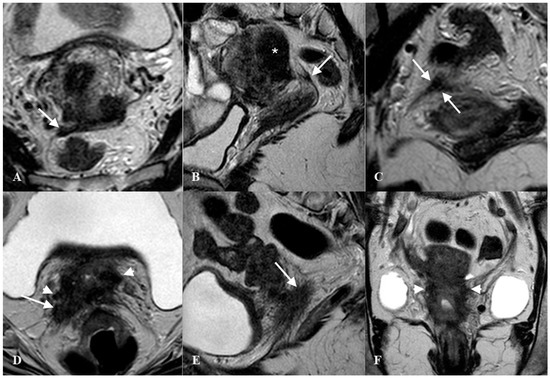

The diagnostic accuracy for endometriosis lesions evaluated using ultrasound has been reported as moderate (sensitivity 0.67, specificity 0.86)[20], which is similar to the accuracy of MRI (sensitivity 0.70, specificity 0.93)[21]. Alcazar et al.[22] assessed parametrial infiltration in cervical cancer and reported a similar diagnostic accuracy for ultrasound (sensitivity 0.78, specificity 0.96), which was also comparable to the performance of MRI. For many years, MRI was the diagnostic gold standard for assessing the extent of lesions palpated with a bimanual combined rectovaginal examination (Figure 6).

Figure 6. Thickened right uterosacral ligament in a woman with deep infiltrating endometriosis and adenomyosis. Axial HR T2w-Turbo Spin Echo (TSE) image (A), Sagittal HR T2w-TSE image (B), Coronal HR T2w-TSE image (C). The right uterosacral ligament shows a nodular thickening (arrows). Diffuse adenomyosis of posterior uterine wall (*). Advanced cervical cancer infiltrating right uterosacral ligament (arrow) and parametrium (arrowhead). Axial HR T2w-Turbo Spin Echo (TSE) image (D), Sagittal HR T2w-TSE image (E), Coronal HR T2w-TSE image (F).